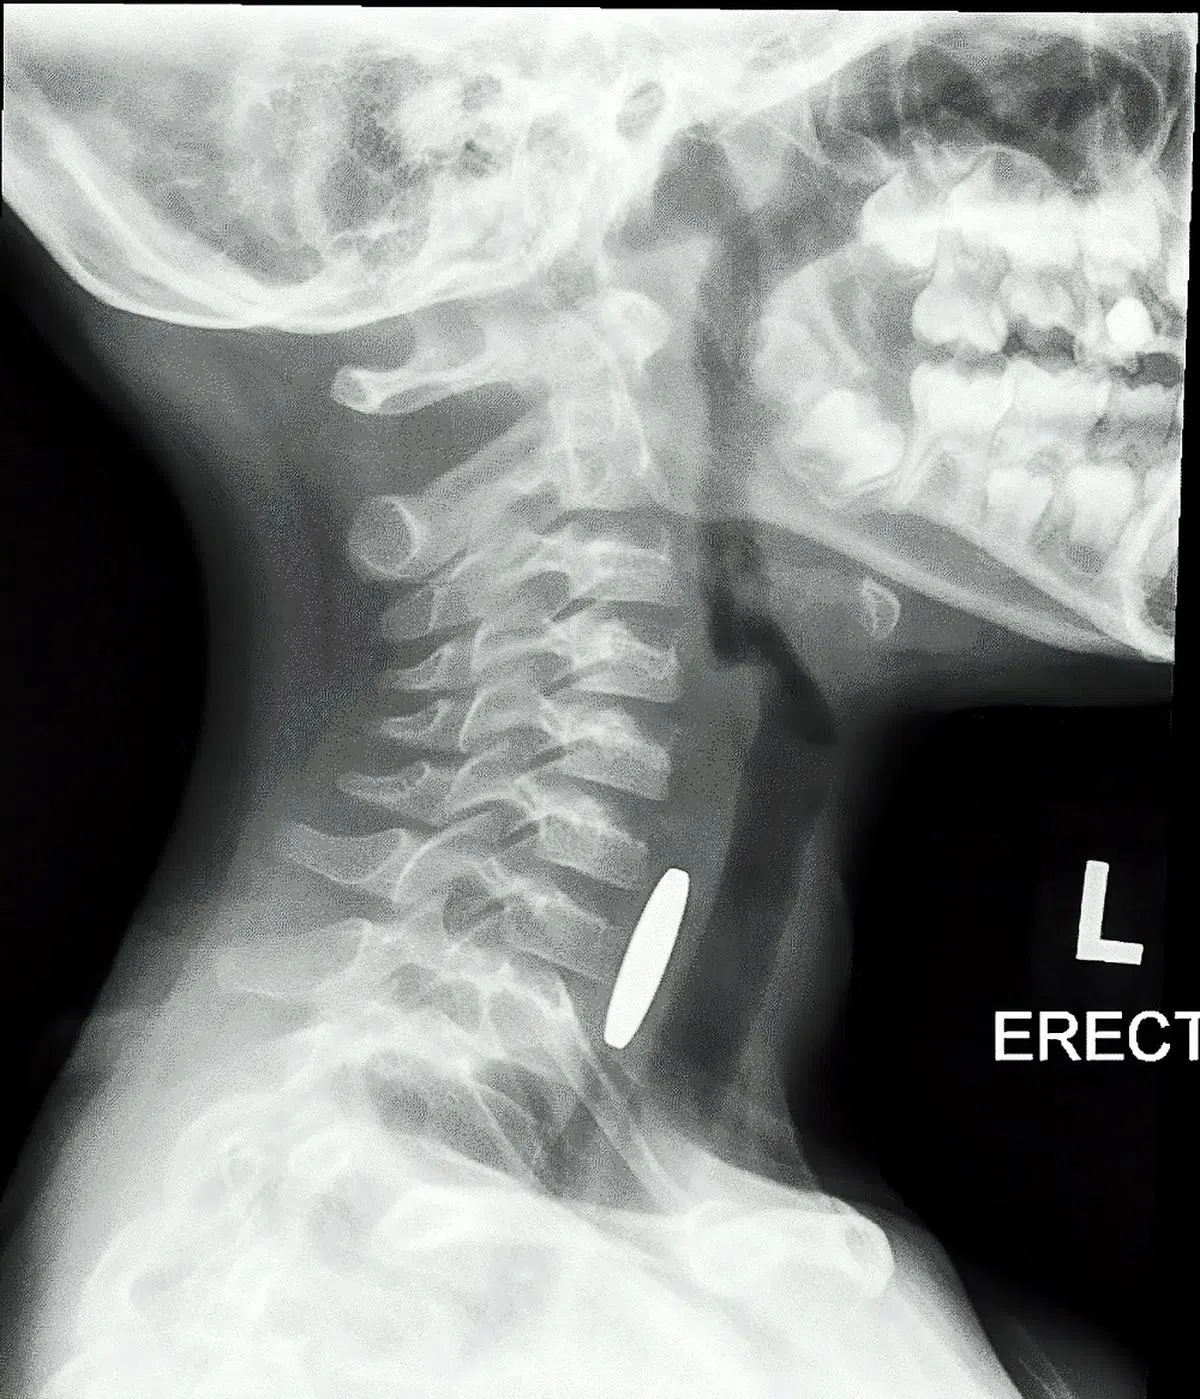

不过,当孩子拒绝进食或开始呕吐,最好去就医。医生一般会通过照X光,确认异物在体内的位置。

图为一名儿童误吞硬币后,硬币卡在食道的X光图像。(新加坡国立大学医院)

如果孩子无法吞咽口水,或过量地流口水,可能是异物滞留在食道,必须利用内窥镜取出。